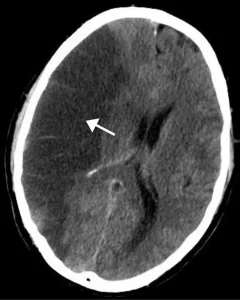

A stroke occurs without warning. It happens “when blood flow to the brain stops, and brain cells in the area begin to die,” as per Healthline.

One of the most important things to do in case of a stroke is to seek medical help as soon as possible. According to the guidelines for the Early Management of Patients With Acute Ischemic Stroke published by the American Heart Association (AHA) and American Stroke Association (ASA) in 2018, people treated with “a blood clot-dissolving drug within 4.5 hours of symptoms have a greater chance of recovering without major disability.”